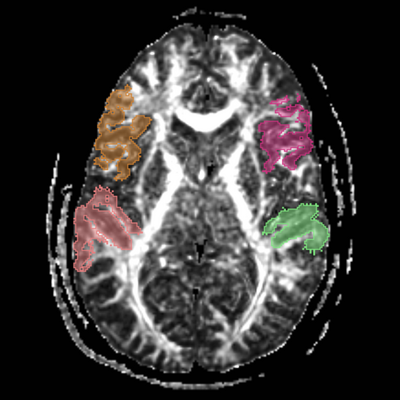

Slicer Hands On Tutorial, August 11, 2010, North Carolina Arcuate.png